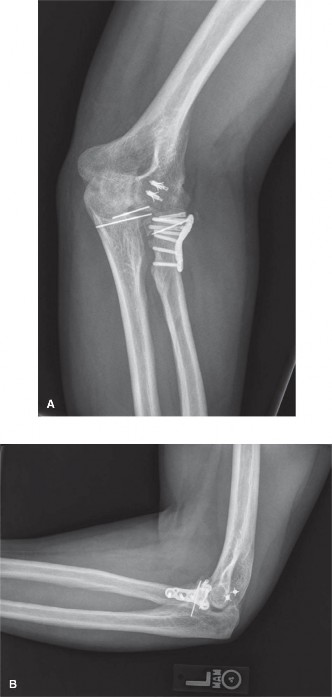

The injury is treated operatively and the post-op radiographs are shown in Figure 6–20A and B. The MCL was found to be competent on intraoperative examination.

Figure 6–20 A–B